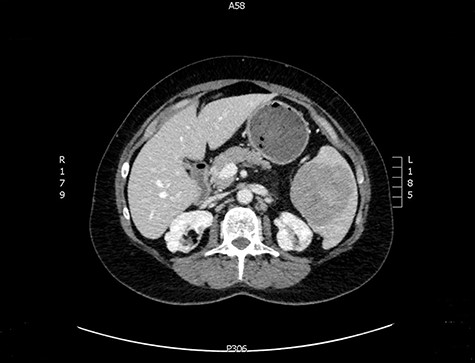

A 57-year-old female was referred from primary care with a 3-year history of generalised fatigue. She has background of ichthyosis, lichen sclerosis, asthma, depression and chronic herpes simplex virus infection. She had hysterectomy due to abnormal smear cells, which was then proven benign on histology. She was initially found to have microcytic anaemia with low ferritin level which did not improve despite oral iron replacement. Both oesophago-gastro-duodenoscopy and colonoscopy were unremarkable. A subsequent computed tomography (CT) scan of the abdomen and pelvis showed a splenic mass with a central area of calcification and a calcified 35 mm pleural-based nodule at the right costophrenic angle.

The latter was discussed in the lung multi-disciplinary team (MDT) meeting. They concluded that the pleural mass was most likely due to post-inflammatory changes. In absence of concerning features, further monitoring or intervention was deemed unnecessary. The splenic mass was then discussed in the hepatobiliary MDT meeting. They recommended obtaining tissue biopsy to aid diagnosis. However, it only showed fibrotic tissue with possible granulomas. The indeterminate histology prompted a repeat CT scan and further magnetic resonance imaging (MRI) to assess the mass further and exclude the possibility of lymphoma. These scans showed stable appearance of the splenic lesion at 6 cm (Figs 1 and 2). The CT scan also picked up numerous small calcifications scattered throughout the peritoneal cavity.